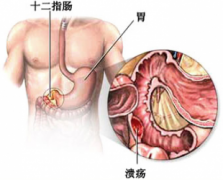

十二指肠球部溃疡的治疗

导读 十二指肠球部溃疡的主要临床表现为上腹部疼痛,可为钝痛、灼痛、胀痛

十二指肠溃疡有哪些症状,什么病因引起的

导语 十二指肠溃疡是消化科常见病之一,十二指肠任何部位都可发生溃疡,但

如何治疗十二指肠溃疡

导读 十二指肠溃疡是消化科常见病之一,十二指肠任何部位都可发生溃疡,但

十二直肠溃疡的症状

导读 十二指肠溃疡是消化科常见病之一,十二指肠任何部位都可发生溃疡,但 查看更多